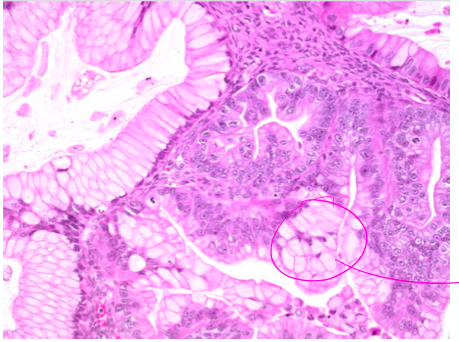

One picture shows healthy endometrium, one shows the patient’s. Which is which?

Picture A is the patient’s

Picture B is normal

What is the patient’s diagnosis?

Endometrioid adenocarcinoma